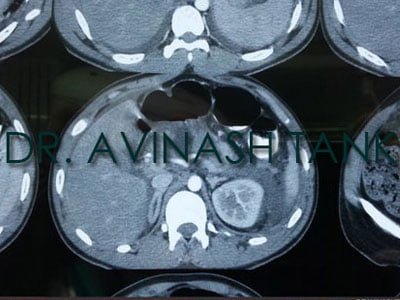

Dr AvinashTank, is a super-specialist (MCh) Laparoscopic Gastro-intestinal Surgeon,

The pancreas is an organ that is about 6 inches long. It’s located deep in your belly between your stomach...